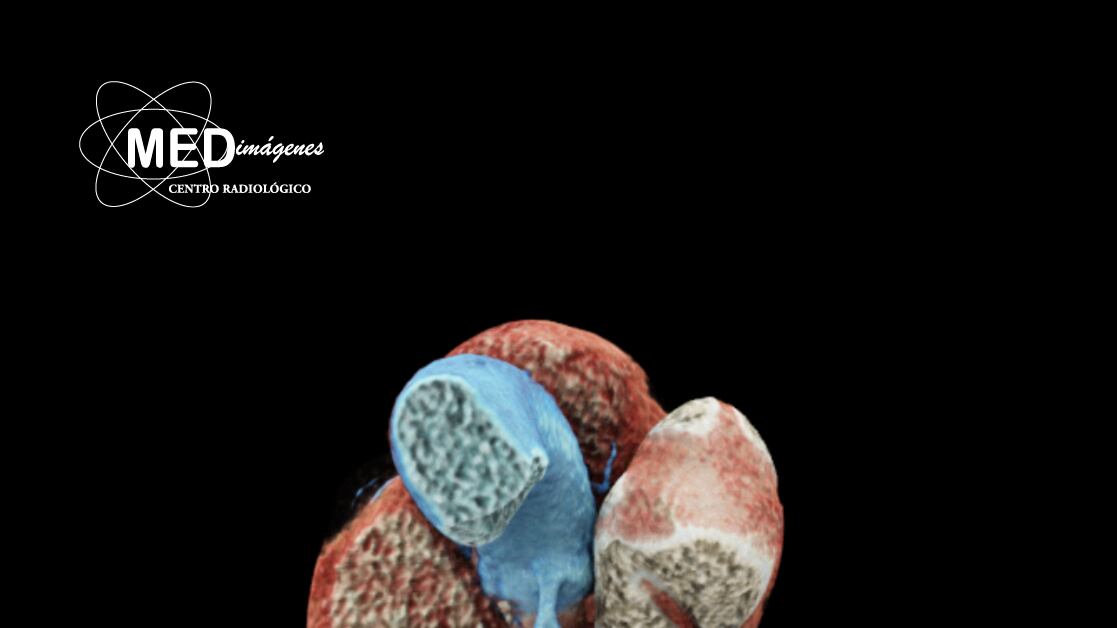

Por ejemplo, exámenes como Score de Calcio, permiten visualizar el riesgo cardiovascular que tiene el paciente y ayuda a determinar si es candidato a algún procedimiento que lo proteja de un posible infarto. También está la Angiotomografía de Coronarias, un estudio muy completo donde se utiliza una pequeña cantidad de contraste yodado, que aporta con gran cantidad de información y permite identificar anomalías congénicas, si se presentan placas de calcio cerca de los vasos, entre otras patologías.

Los tomógrafos de última generación, como el Somaton® go.Top, aporta con imágenes tan descriptivas que permiten ver el tamaño que tiene el corazón y comprender de mejor manera lo que se requiere para mejorar su salud. En esta porción del tórax, también se analiza el estado del pericardio, los pulmones y costillas que también puede generar molestias en esta área del cuerpo.